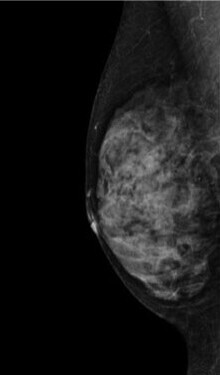

検査結果では、乳房の構成を以下4つに分類してお知らせします。

1.脂肪性

2.乳腺散在

3.不均一高濃度

4.極めて高濃度

3・4に該当する乳房は「高濃度乳房(デンスブレスト)」と呼ばれ、乳腺が白く映るためマンモグラフィのみでは異常が隠れてしまうことがあります。

そのため、マンモグラフィ検査と乳腺超音波検査の併用を強くおすすめします。

症状がなくても、高濃度乳房と判定された方は積極的な併用検診が早期発見につながります。